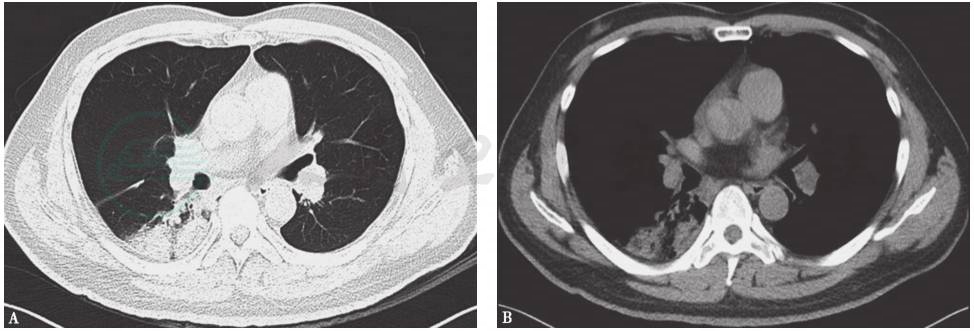

胸部CT、支气管动脉CT血管造影(CT angiography,CTA)和CTPA显示:①双肺动脉主干及分支多发栓塞(图2),右下肺渗出性实变(图3);②双侧支气管动脉未见扩张;③双侧少量胸腔积液。

图2 CTPA表现

CTPA显示双肺动脉主干及分支多发栓塞